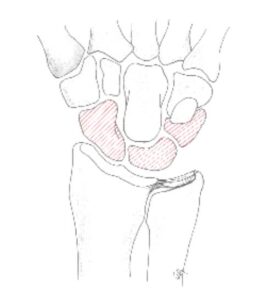

Diagram van de botjes die verwijderd worden bij proximale rij carpectomie. (Links) Radiografie van pols na proximale rij carpectomie (Rechts).

- Proximale rij resectie: het weghalen van de 1e rij handwortelbeenderen. Dit zorgt voor een voorspelbare afname van de pijn, echter er blijft een krachtsverlies en de pols verliest ongeveer 50% beweeglijkheid ten opzichte van een gezonde pols. Via een lengtesnee aan de rugzijde van de pols worden deze botjes weggehaald waardoor de 2e rij handwortelbeenderen met de onderarm een nieuw pols gewricht vormt.